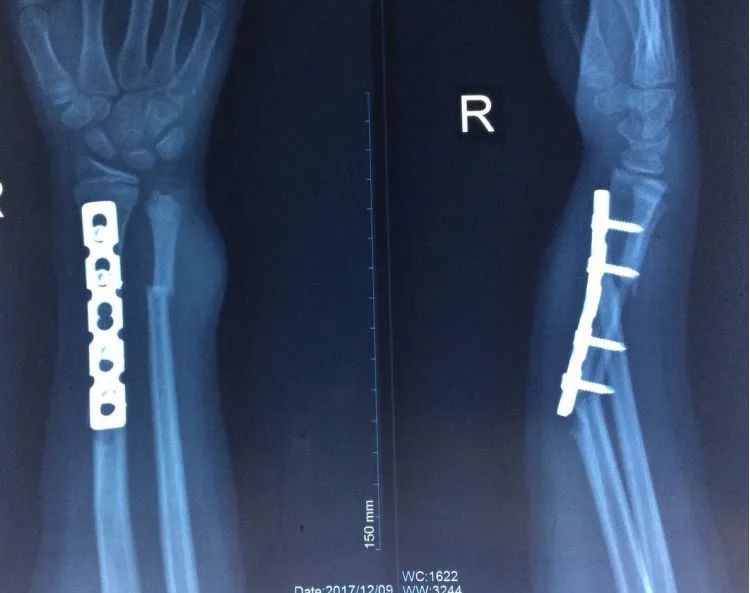

胫骨远端简单骨折选用钢板固定没有实现坚强固定,钢板承受应力,孔处应力集中断裂

更换长钢板后愈合